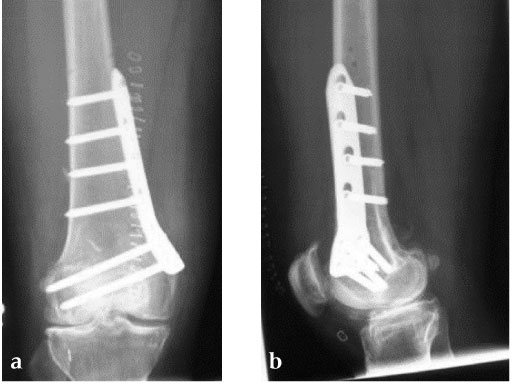

27-year-old male developed severe lateral joint line pain after lateral menicectomy.

Case provided by Philipp Lobenhoffer, Hannover, DE

The Patient can be mobilised as early as day one after surgery. Partial weight bearing is recommended for 6 weeks, active movement of the knee is encouraged. X-ray control after 6 weeks should demonstrate bony healing. Full weight bearing can be allowed in many cases after this time period, if the osteotomy site is still painful and bone healing is incomplete, weight bearing should be delayed for further 34 weeks.

An anteromedial skin incision is used. This skin incision can be reused and expanded during subsequent knee surgery. The vastus medialis muscle is dissected from the septum, the medial patellofemoral ligament (MPFL) and the distal insertion of the vastus medialis muscle are partially incised. Two blunt Hohmann retractors are placed around the distal femur. The oblique osteotomy starts in the medial supracondylar area and ends in the lateral condyle, approximately 10 mm inside the lateral cortex. For guiding the closing wedge osteotomy of the distal femur a specific saw guide will be available soon. Alternatively, it is possible to use K-wires inserted under image intensifier control to mark the bone cuts. The saw cuts are made with retractors protecting the soft tissue and vessels. The wedge is removed and the height and depth of the osteotomy can be measured. At this time it is possible to make modifications concerning the wedge size. Closing the wedge must be done gradually by gentle compression of the lower leg laterally, and stabilizing the knee joint medially near the area of osteotomy. This may take several minutes to enable plastic deformation of the lateral cortex to close the osteotomy gap. Leg alignment is checked radiologically after closing with a rigid alignment bar positioned between hip and ankle center. The bar representing the weight-bearing line should pass the preoperatively defined mechanical axis. The plate is inserted from distal under the vastus medialis muscle. The distal drill holes are oriented in a 20 angle inclination on the frontal plane to avoid a posterior perforation of locking head screws in the distal femur. The distal four bolts are placed. A lag screw is positioned in the dynamic hole directly above the osteotomy for compression of the osteotomy site. The screw should be tightened carefully using the image intensifier. The plate is now fixed to the shaft with bolts monocortically, and the lag screw is replaced by a bolt bicortically. The wound is closed in layers after insertion of a drain. The patient is mobilized on the first day after surgery. Partial weight bearing is recommended for 6 weeks, active movement of the knee is enhanced. Biomechanical testing confirmed superior stability of medial closing wedge techniques as compared to lateral open wedge techniques and favourable axial and torsional loading characteristics of the TomoFix medial distal femur (MDF) plate. The plate is now available, as well as a booklet on the operative technique.